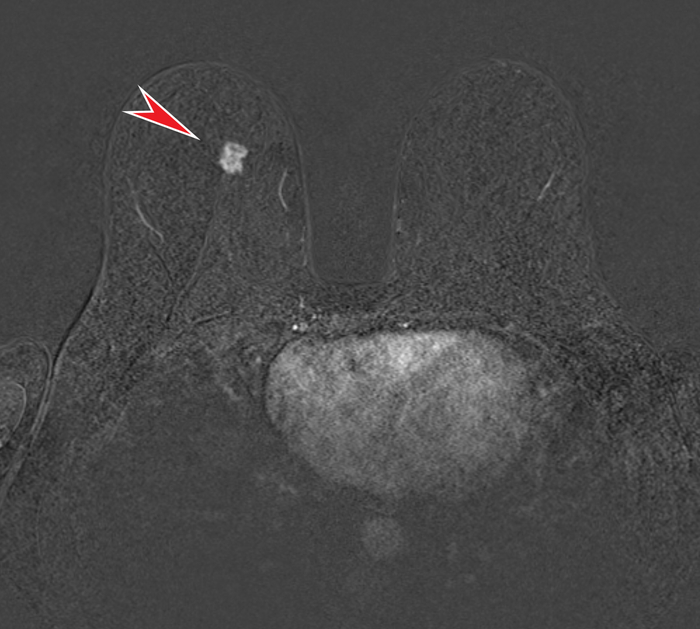

А также относительно гомогенным набором контрастного вещества в раннюю артериальную фазу (т.е. непосредственно сразу после внутривенного введения):